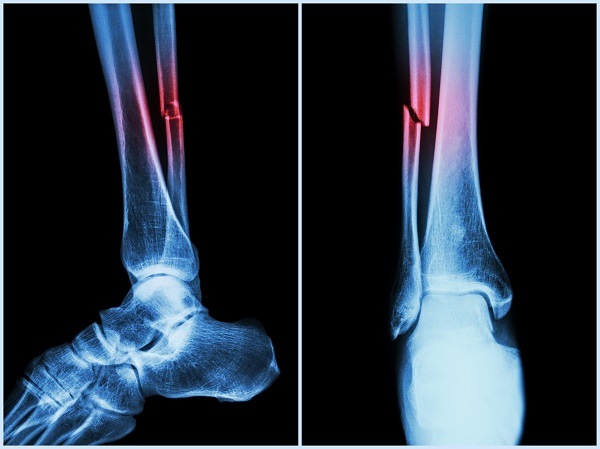

What is a Transverse Fracture?

A Transverse Fracture is a straight break across the bone, typically caused by a direct force applied perpendicular to the bone.